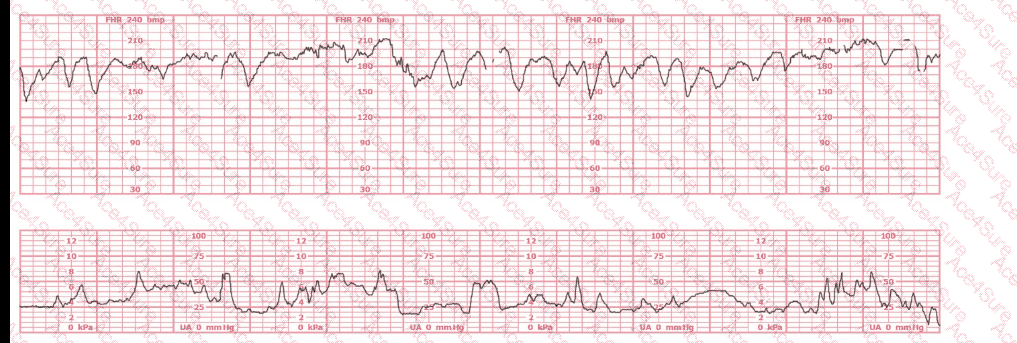

The tracing demonstrates:

Baseline ~150 bpm

Variability ≥ 25 bpm amplitude, highly erratic and wide

No sustained decelerations

No sustained accelerations ≥ 2 min

NICHD/NCC definition of marked variability:

Amplitude of baseline FHR fluctuations greater than 25 bpm.

Thus, the correct interpretation is A. Marked variability.